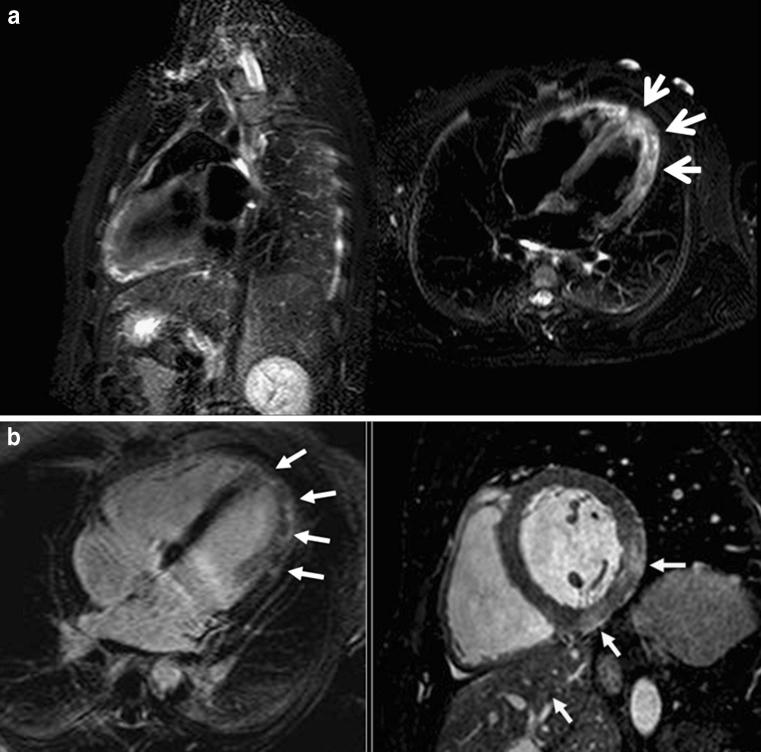

Left ventricular apical diseases.

There are many disorders that may involve the left ventricular (LV) apex; however, they are sometimes difficult to differentiate. In this setting cardiac imaging methods can provide the clue to obtaining the diagnosis. The purpose of this review is to illustrate the spectrum of diseases that most frequently affect the apex of the LV including Tako-Tsubo cardiomyopathy, LV aneurysms and pseudoaneurysms, apical diverticula, apical ventricular remodelling, apical hypertrophic cardiomyopathy, LV non-compaction, arrhythmogenic right ventricular dysplasia with LV involvement and LV false tendons, with an emphasis on the diagnostic criteria and imaging features. ELECTRONIC SUPPLEMENTARY MATERIAL: The online version of this article (doi:10.1007/s13244-011-0091-6) contains supplementary material, which is available to authorized users.